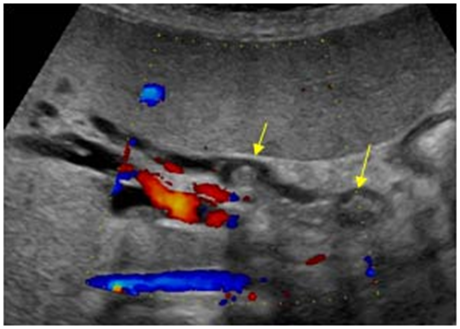

3. Vascular compression or invasión (Figure 7)

Figure 7 Compresion and invasion of the splenic vein.